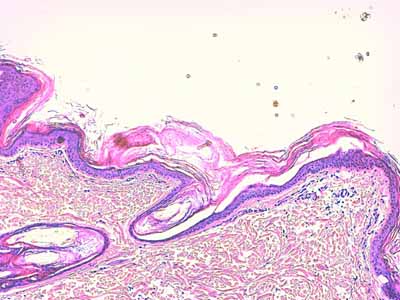

L’épiderme présente une hyperkératose orthokératosique compactée qui reste alvéolaire et laminée (Photo 2).

Cette hyperkératose compactée ponte souvent l’abouchement de follicules pileux (Photo 3). Au sein des couches épineuse et granuleuse, les kératinocytes apparaissent régulièrement vacuolisés, sous la forme d’une vacuole cytoplasmique unique en couronne péri-nucléaire, donnant l’impression que le noyau de ces kératinocytes est contenu dans une petite logette optiquement vide (Photo 7).

Photo 3 (Hémalun Eosine X 100) : l’hyperkératose orthokératosique de

l’épiderme “ponte” l’abouchement des ostia folliculaires. Le derme est silencieux.

Légendes de la Photo 3 :

- Pointe de flèche turquoise : hyperkératose orthokératosique

- Ovale jaune : ostium folliculaire hyperkératosique

- Double flèche pointillée rouge : des lamelles de kératine orthokératosique parallèles à l’épiderme, pontent l’abouchement d’un ostium folliculaire

- Double flèche verte : épaisseur épidermique

- Double flèche pointillée noire : épaisseur dermique